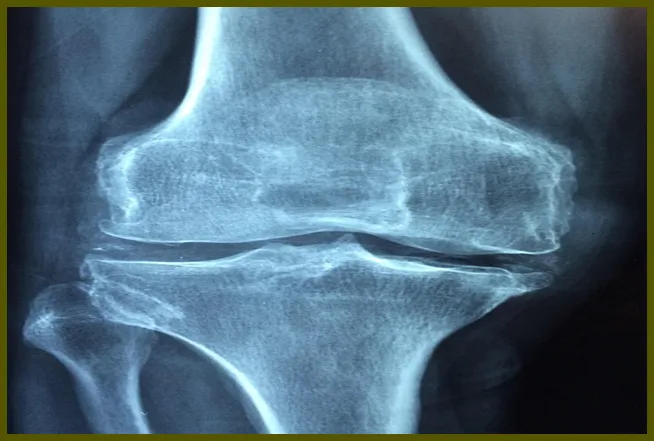

무릎 관절염

관절염은 무릎 안쪽 통증의 주요 원인 중 하나입니다. 이 질병은 관절의 염증으로 인해 발생하며, 통증과 부종을 유발할 수 있습니다. 퇴행성 관절염은 노화와 관련이 있으며, 관절의 연골이 닳아 없어지는 것이 원인입니다. 젊은 층에서도 발생할 수 있는 류마티스 관절염 역시 무릎 통증을 일으킬 수 있는 중요한 요인입니다.